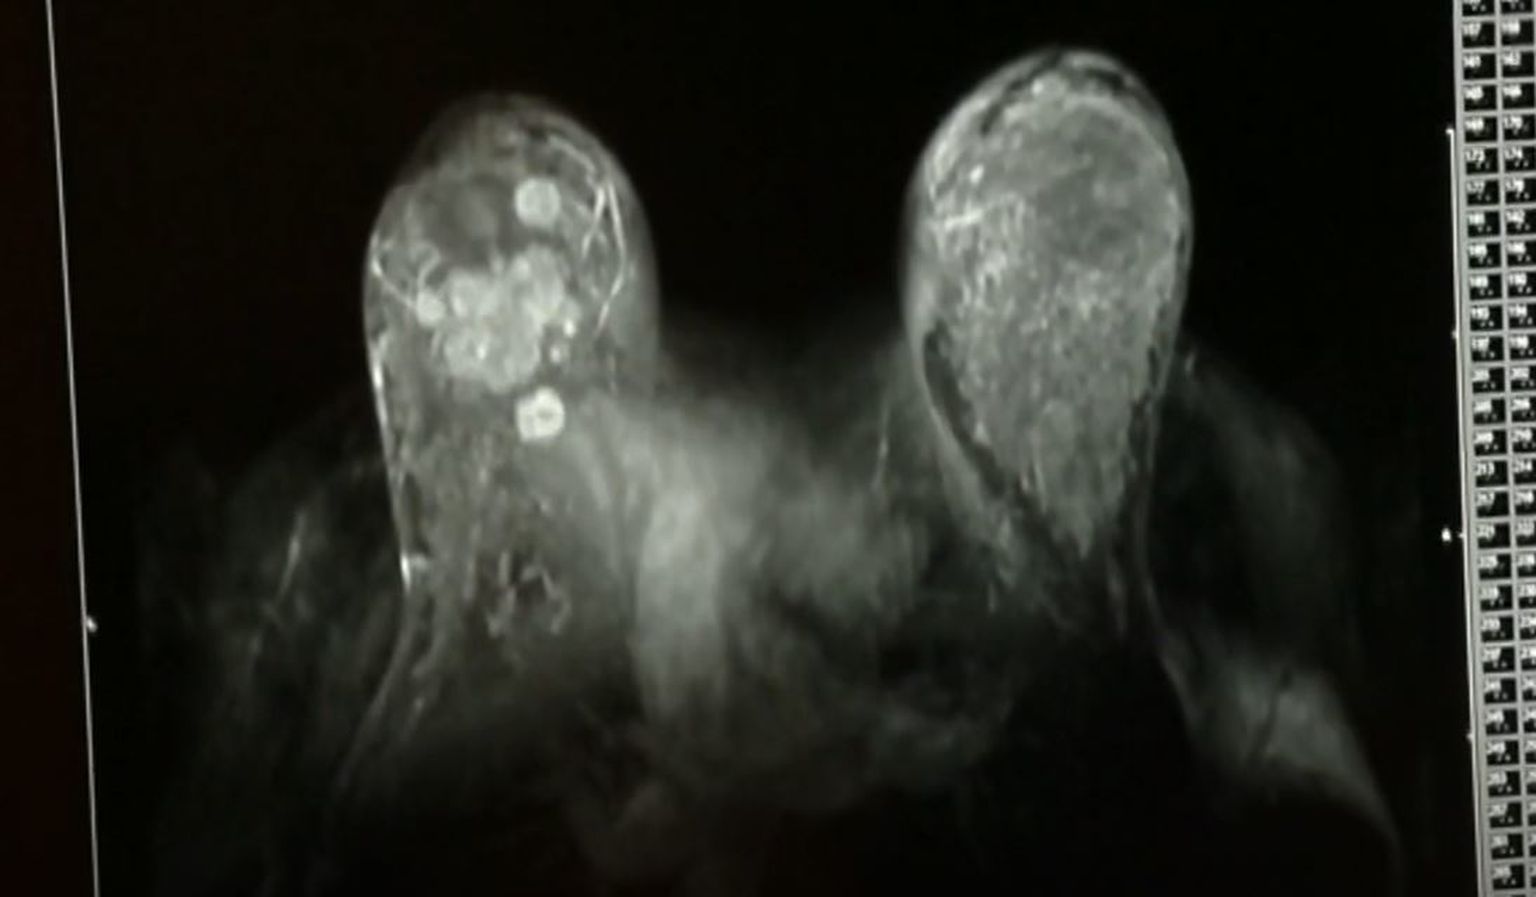

Liste čekanja na pretrage sve su duže, još traju problemi s veledrogerijama... a gdje je reforma zdravstva?

Nikad više pritužbi na zdravstvo! Pravobraniteljica: "Građani nekad nemaju ni osnovnu informaciju, a ovo zahtijeva potpuni remont"